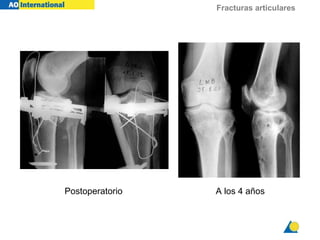

A los 4 añosPostoperatorio

Fracturas articulares A los4 añosPostoperatorio